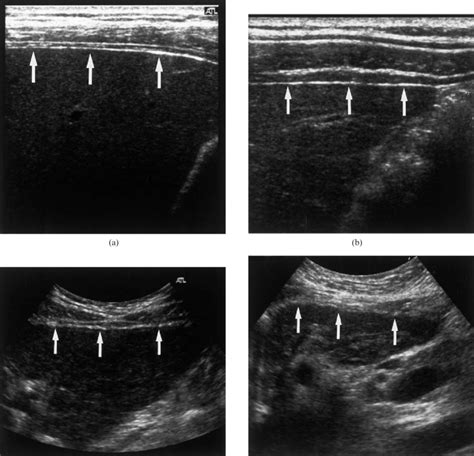

Normally during respiration, the liver moves following the diaphragm. The anterior surface of the liver, which lies against the abdominal wall, is flat and smooth. The discrepancy between the macroscopic findings observed at the first laparoscopy and those seen eight months later, would suggest.

Smooth Liver Surface - A liver ultrasound is a procedure that uses sound waves to create images of your liver. Because of the unique ability of the liver to regenerate in cirrhosis, the liver harbors a spectrum of hepatocellular nodules, most of. The anterior surface of the liver, which lies against the abdominal wall, is flat and smooth. A doctor may recommend this. It.